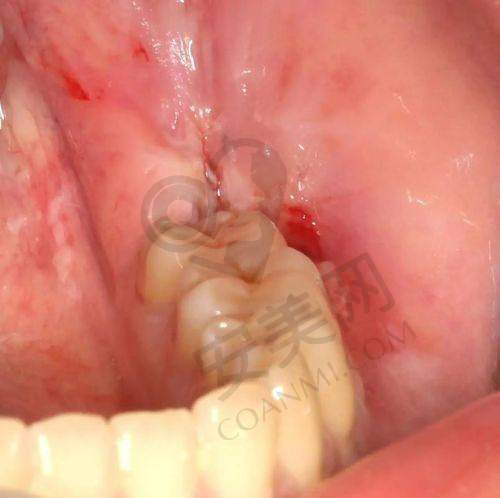

玉溪舒尔口腔医院的智齿拔除价格分为不同阶段。380元起的价格是基础价位,针对的是一些比较容易拔除的智齿,比如已经完全萌出,位置比较正,拔除难度相对较低的智齿。对于这类智齿,医生操作相对简单,所需时间也较短。而对于一些位置比较特殊的智齿,价格则会相应提高。例如,部分埋伏在牙龈下的智齿,需要先切开牙龈,去除部分牙槽骨才能拔除,这种情况下价格可能在800 - 1500元左右。还有一些完全埋伏在颌骨内的智齿,拔除难度更大,手术过程更复杂,价格可能会超过1500元。需要强调的是,以上价格仅供参考,实际价格会根据智齿的具体情况和患者的个体差异有所不同。